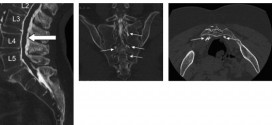

Leer MásEspondilodiscitis

La Espondilodiscitis lumbar (EDL) o vertebral es una Inflamación de una vértebra y el disco intervertebral adyacente; suele ir acompañada de dolor y rigidez en el segmento afectado. Debido a una infección del disco intervertebral adyacente que afecta al cuerpo vertebral y se puede extender a sus vecinos contiguas (cuerpos vertebrales adyacentes, paravertebral y prevertebral, espacio epidural, etc.). La vía …

Leer MásESPONDILOARTOSIS (artrosis de la columna vertebral)

La espondiloartrosis o Artrosis de la columna vertebral o artrosis lumbar, es una degeneración de los cartílagos articulares. Afecta con mayor frecuencia a la columna vertebral, sobre todo a los segmentos cervicales y lumbares que se caracteriza por alteraciones del disco intervertebral y del cartílago, Osteoclerosis subcondral y formación de osteofitos. La sintomatología es muy característica: dolor lumbar que aumenta …